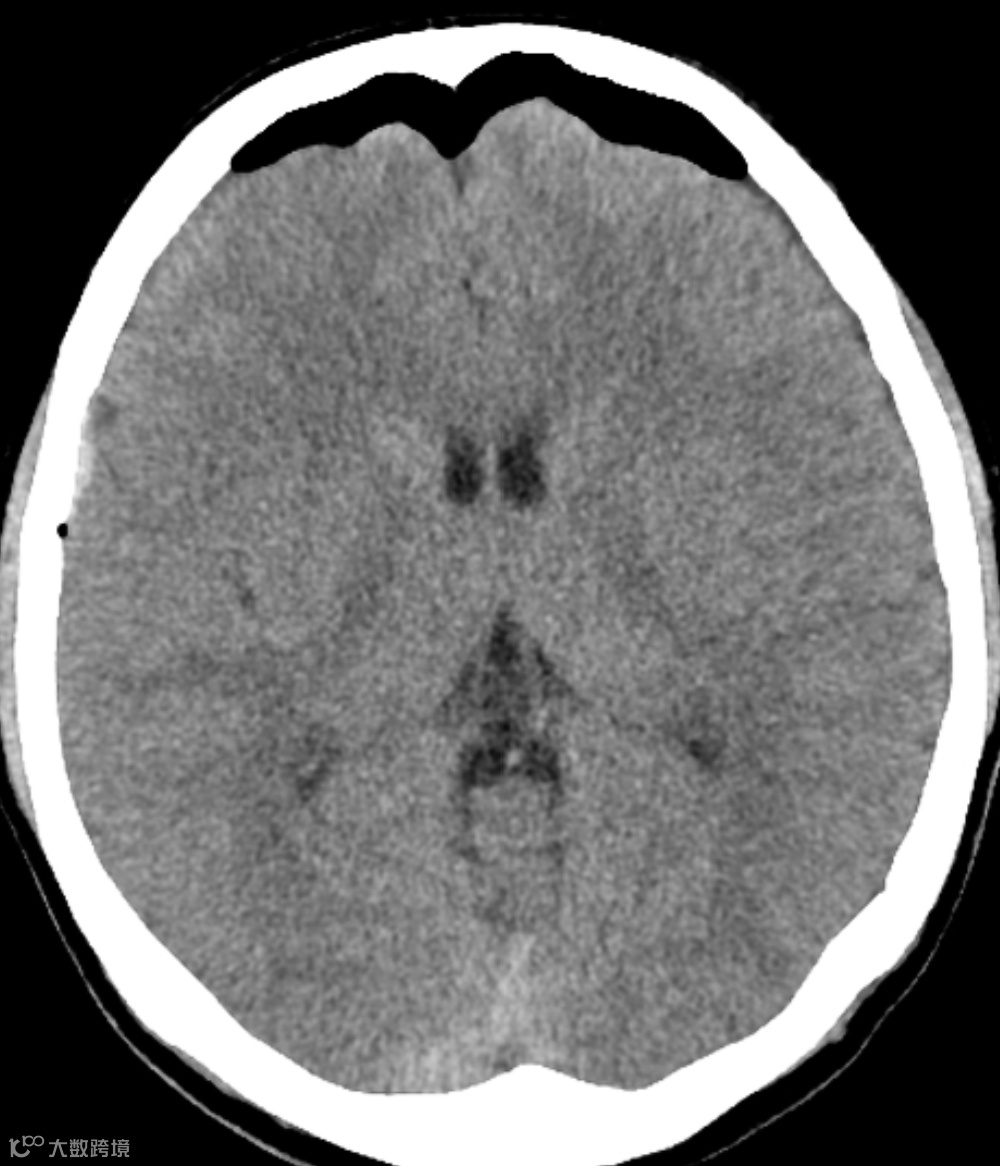

患者,男,30岁,头部受伤后昏迷。

头颅CT显示双侧额极硬膜下腔积气,呈富士山征。

张力性气颅初始,高张力的气体可压迫邻近脑组织(通常见于额叶),额叶被推到一起、变尖及移位,在中线处形成山峰样改变,即山峰征,周围是空气。

随着病情的发展,颅内气体增多,额叶开始分离,坍塌的额叶和额极大脑半球间的裂隙增宽而出现富士山样的轮廓,称为富士山征。